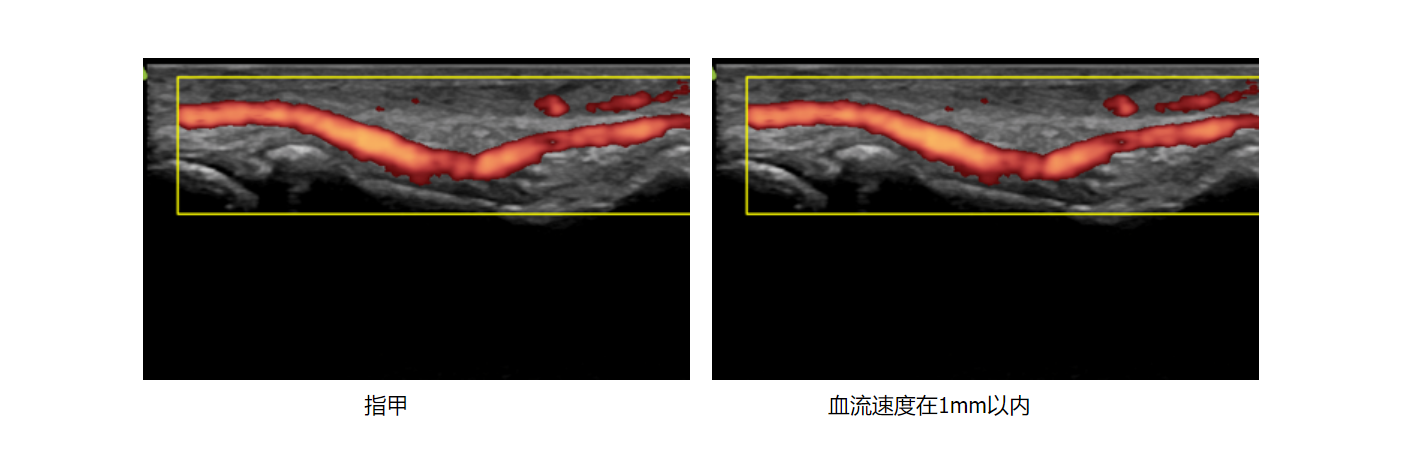

微磁导航—体外精准定位

小鼠主动脉弓 小鼠肾脏血流